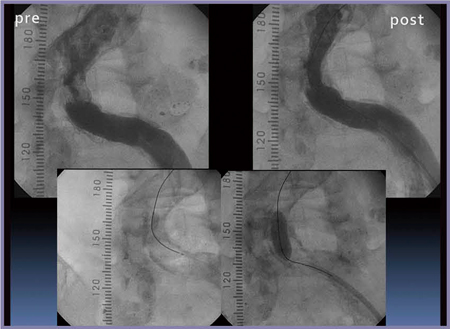

浅大腿動脈(SFA)病変では,穿刺プランにも冠動脈CTAが有用である。穿刺部と病変部の間にどれくらいのマージンがとれるかによって,穿刺位置を同側とするか対側とするかが変わるため,重要なポイントとなる。

症例6では,病変部まで15cmのマージンがあることが確認できたため,同側からシースを挿入し,ステントを留置した。

図12 症例6:PTA術前(左)・術後(右)のCAG